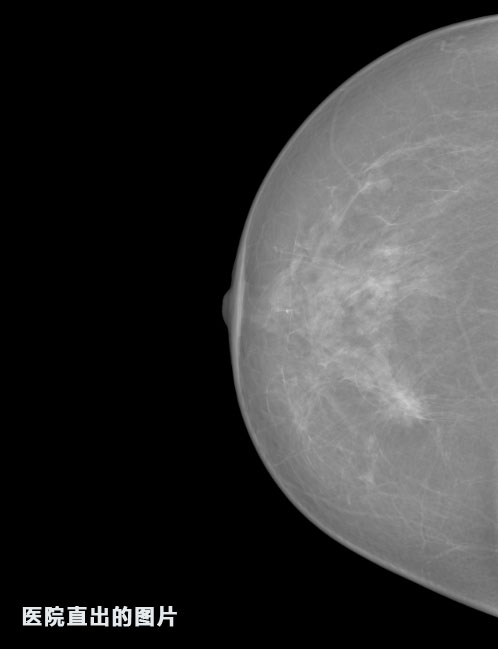

識別報告:

1.發(fā)現良性鈣化,可能性為19.88%---位置框指數:[1796.0867 1359.8237 2058.1372 1582.5334]

2.發(fā)現惡意鈣化的可能性為15.18%---位置框指數:[1789.4733 1365.9951 2063.7698 1576.0613]

3.發(fā)現惡意鈣化的可能性為12.45%---位于框指數:[1859.3987 1422.3184 2006.5494 1528.2698]